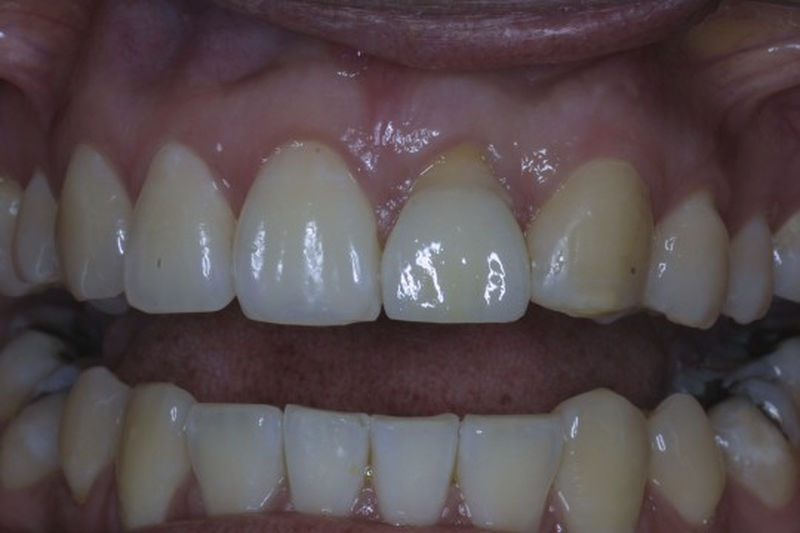

Amplia gama de tratamientos para mejorar la apariencia de la sonrisa, corrigiendo el color, la forma, el tamaño, la alineación y la posición de los dientes. Los procedimientos más comunes y solicitados incluyen el blanqueamiento dental, las carillas y coronas, así como las resinas.

Son restauraciones que cubren toda la cara frontal del diente, generalmente empleadas en el sector anterior y cuya finalidad es primariamente estética.

Restauraciones fabricadas en el laboratorio con materiales estéticos, los cuales cubren de manera total dientes anteriores y posteriores. Se utilizan primariamente para restaurar dientes con caries, fracturas y/o defectos amplios, así como soportes de puentes. Para poder enviar el caso al laboratorio se toman impresiones utilizando materiales de impresión o técnicas modernas digitales.